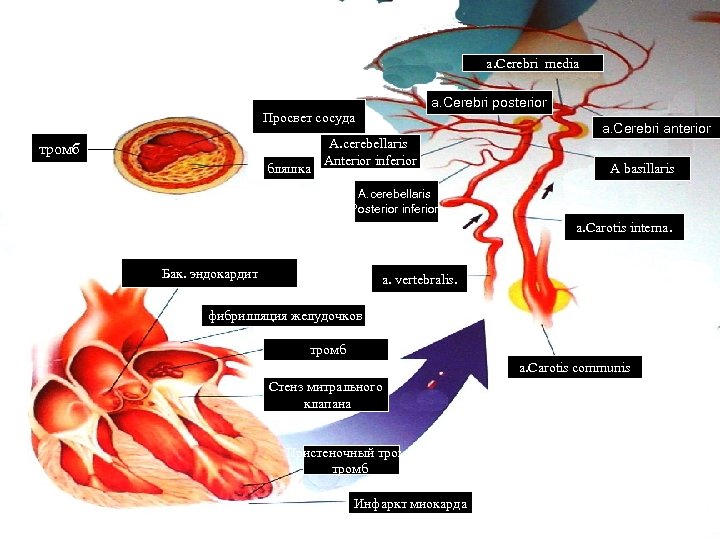

a. Cerebri media a. Cerebri posterior Просвет сосуда тромб бляшка А. cerebellaris Anterior inferior a. Cerebri anterior A basillaris А. cerebellaris Posterior inferior a. Carotis interna. Бак. эндокардит a. vertebralis. фибрилляция желудочков тромб a. Carotis communis Стенз митрального клапана Пристеночный тромб Инфаркт миокарда

a. Cerebri media a. Cerebri posterior Просвет сосуда тромб бляшка А. cerebellaris Anterior inferior a. Cerebri anterior A basillaris А. cerebellaris Posterior inferior a. Carotis interna. Бак. эндокардит a. vertebralis. фибрилляция желудочков тромб a. Carotis communis Стенз митрального клапана Пристеночный тромб Инфаркт миокарда